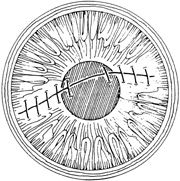

Placement of sutures through the visual axis should be avoided. If it is necessary to pass sutures near the visual axis, they may be placed on each side of, but not directly through, the axis itself. In addition, the bite closest to the visual axis may be made shorter, thus avoiding this area (Fig. 6). A “no-touch” technique also may be used to minimize trauma at the visual axis. With this technique, the eye is secured by grasping the globe with forceps away from the cornea. The suture needle end is then placed perpendicular to the corneal surface, and the needle is rotated through the corneal tissue following the needle's curvature (Fig. 7).8

With more complex lacerations, good wound apposition with minimal distortion is the goal. An irregular wound is first subdivided into straight segments with interrupted sutures. Perpendicular areas of the laceration should be sutured before beveled ones to achieve watertight closure with the fewest number of sutures. As suggested by Rowsey and Hays,7 long, deep, and relatively tight peripheral wound sutures in combination with shorter, shallower, appositional sutures near the visual axis may help restore the normal corneal contour by restoring the relatively steep central corneal dome (Fig. 8). For irregular or curvilinear lacerations, all interrupted sutures should be placed perpendicular to the wound, thus avoiding transverse shifting of the wound margins. Although a running shoestring suturing technique may be used with straight lacerations to minimize astigmatism and facilitate subsequent suture removal, a running suture may tend to distort an irregular or curvilinear laceration because it will tend to form a straight line. Thus, if used, running suture bites should be placed perpendicular to and equidistant from an imaginary “regression” line through the wound rather than with respect to the wound itself (Fig. 9).